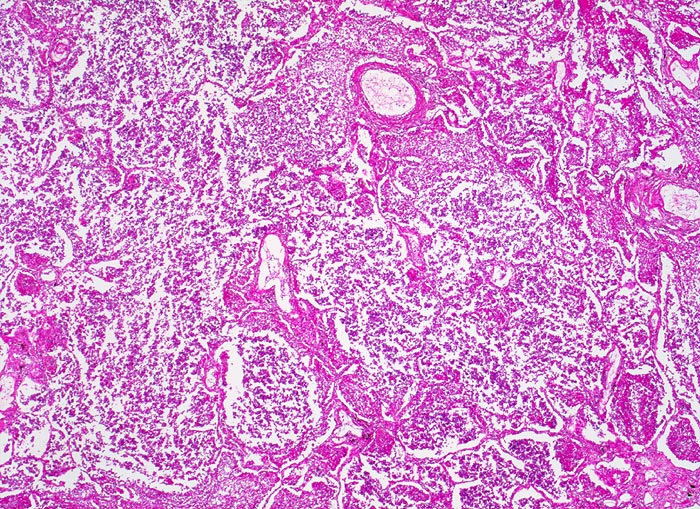

Lobärpneumonie

Alle Alveolen sind gleichmässig und diffus befallen und im selben Stadium der Entzündung. Sie sind angefüllt mit fädigem Fibrin und neutrophilen Granulozyten.

Der linke Lungenunterlappen ist vergrössert und verfestigt. Die Schnittfläche ist leicht körnelig und graugelb. Der Abstrichsaft ist gelblich trüb und schmierig. Die übrigen Lungenlappen sind leicht ödematös.

Eine Lobärpneumonie tritt auf, wenn die Erreger die Alveolarräume so ausgedehnt und rasch befallen, daß sie erst vor anatomischen Grenzen (z.B. einem Lappenspalt) Halt machen.